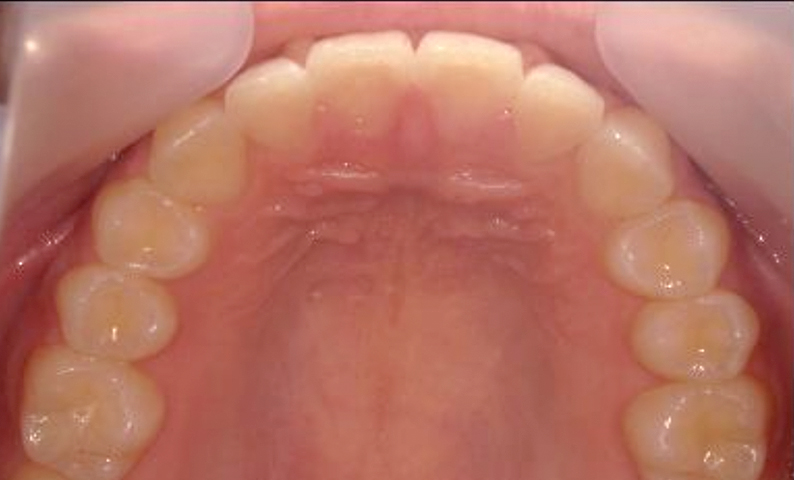

症例_004 上顎だけの部分矯正

治療期間:6ヶ月金額:27万円+税男性出っ歯上の前歯だけ

| Before | After |